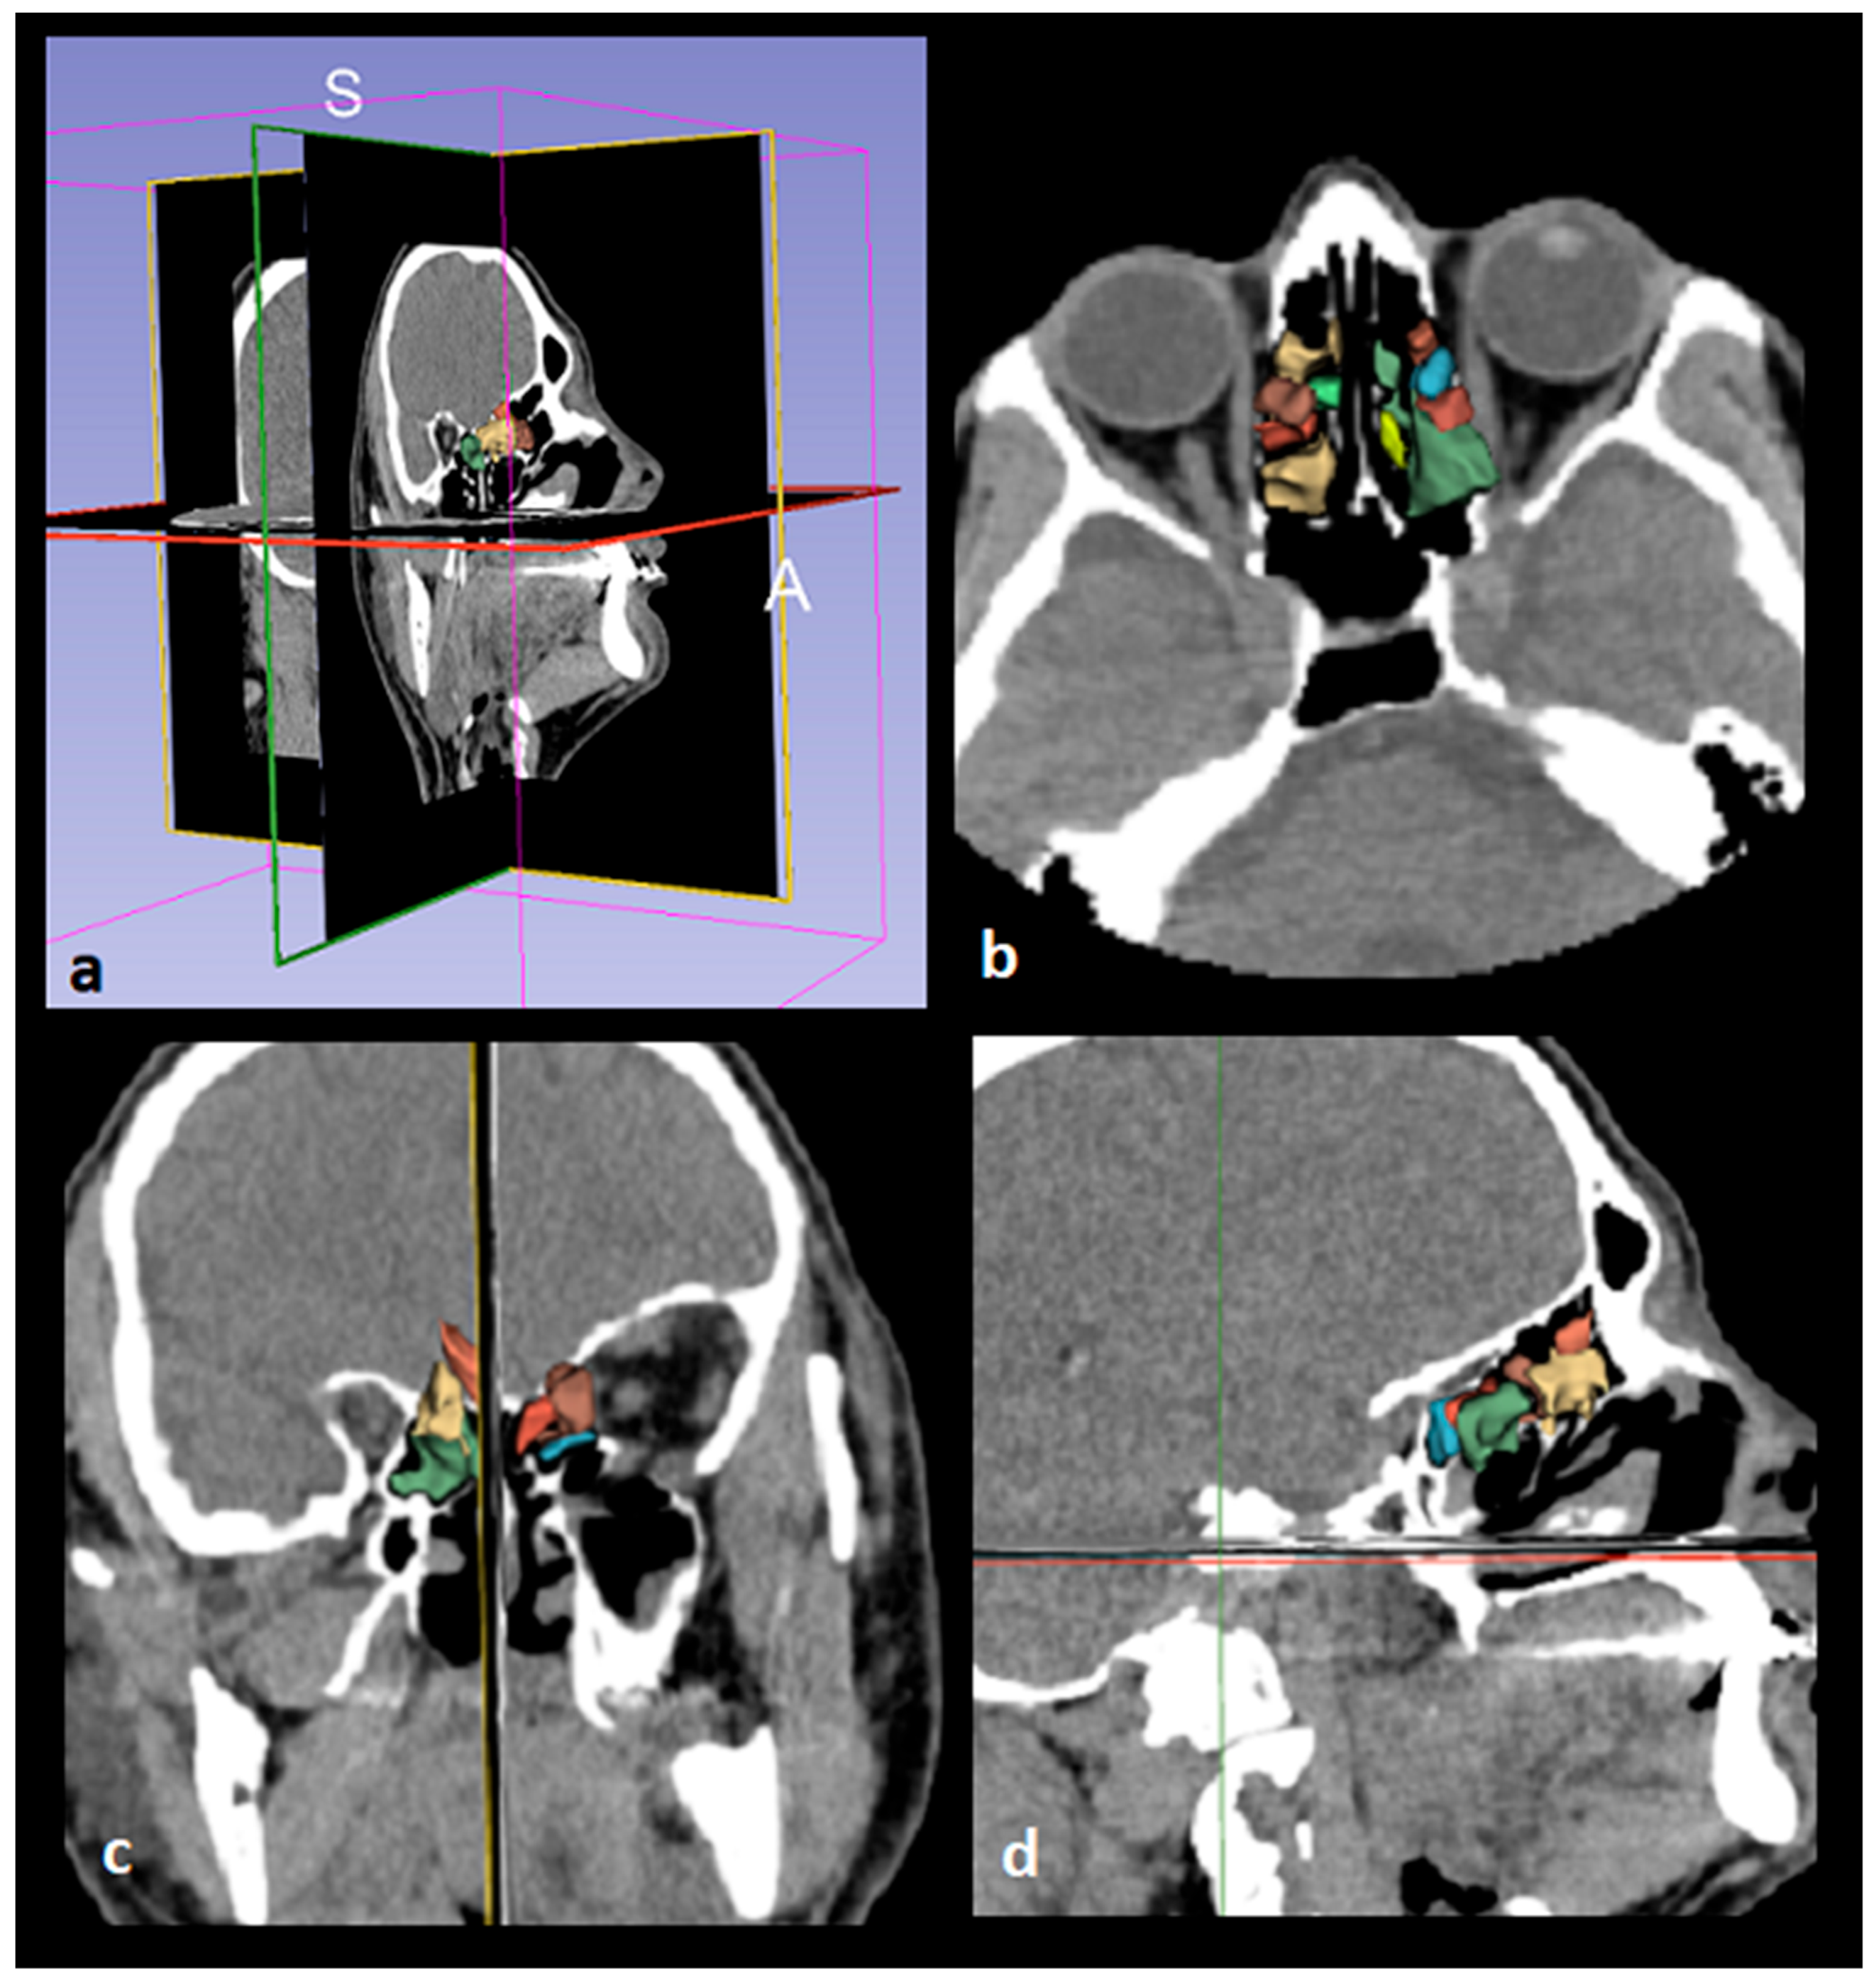

We obtained subjects' CT images from our hospital's Picture Archiving and Communication System (PACS) and saved them in Digital Imaging and Communications Medicine (DICOM) format. DICOM data were then transferred to a personal computer. 3D Slicer (https://www.slicer.org/, version 5.3.1), a fully automated open-source software, was used for analysis (accessed on 5 Sep 2025) [9]. Images were displayed in the axial, coronal, and sagittal planes using the 3D Slicer application, and segmentation was performed (Figure 3 and Figure 4). The following steps were followed to select images suitable for segmentation and perform volumetric measurements.

Figure 3. Images demonstrating the fully automated segmentation of the ethmoid sinus by the 3D Slicer application. Axial, coronal and sagittal views are shown in b, c and d, respectively.